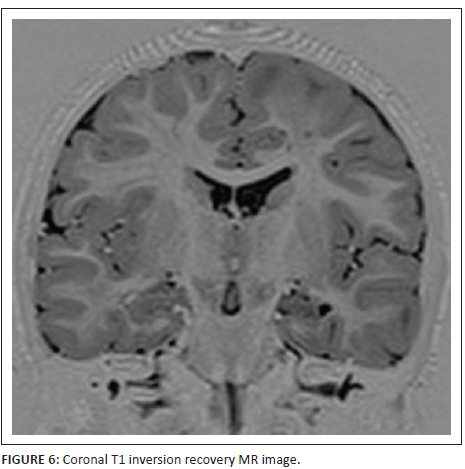

Figures 4 and 6 are coronal T1- inversion recovery sequence images and Figure 5 is a coronal T1-weighted image - all three confirming that the subependymal nodules are probably tubers. Also further delineating the cortical-subcortical hamartomas, left hippocampal signal abnormality and adjacent transmantle left temporal lobe band.